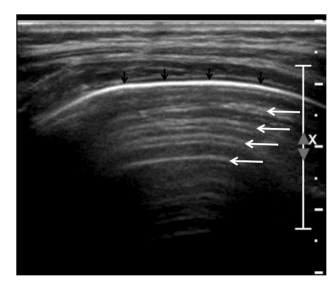

Также врач оценивает так называемые A-линии (см. рис. 1) — повторяющиеся горизонтальные сигналы, которые обычно указывают на нормальное состояние лёгочной ткани.

Рис.1 А-линии проявляются в виде множественных артефактных гиперэхогенных равноудаленных линий (белые стрелки), параллельных плевральной линии (черные стрелки), и присутствуют в нормальных аэрированных легких.

Если же появляются вертикальные «лучи» — B-линии (см. рис. 2), это может говорить о наличии воспаления или жидкости в лёгких. При этом сами по себе они не дают точный диагноз, но помогают понять, что в ткани есть изменения.

Рис.2 B-линии представляют собой вертикально ориентированные артефактные гиперэхогенные линии, которые берут начало от плевральной линии (стрелки), простираются к нижней части экрана и движутся синхронно со скольжением легкого. Наличие множественных B-линий, как показано здесь, указывает на интерстициальный процесс в легких